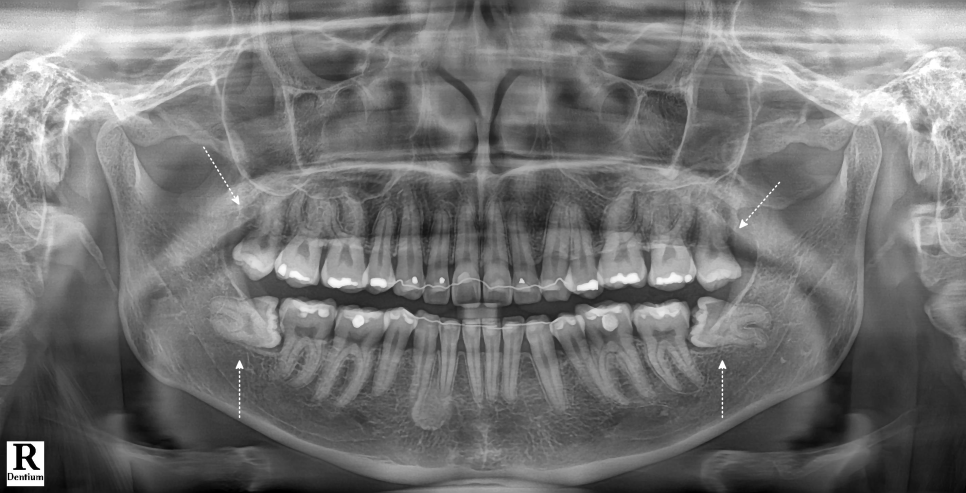

엑스레이를 보고 바로 느낀 건 ‘쉽지 않다’였어요.

잇몸 속에 묻혀 있는 형태는 육안으로 확인하기가 힘들어서 엑스레이를 통해 정확한 상태를 확인해 봤는데요.

위쪽은 똑바로 나있었지만 아래 사랑니가 모두 매복 되었고 뿌리가 두 갈래로 갈라져 있었으며, 끝이 많이 휘어 있는 형태였어요.

또, 뿌리 끝과 하치조신경관의 거리가 매우 가까웠는데요.

이런 경우, 발치하다가 하치조신경관이 손상되는 경우도 있어서 매우 조심해야 됩니다.

뿌리와 엑스레이를 보면서 잘 나온 것 같았지만, 더블 체크를 위해 엑스레이를 촬영했어요.

촬영일 : 251121

깔끔하게 제거된 것을 볼 수 있었어요.